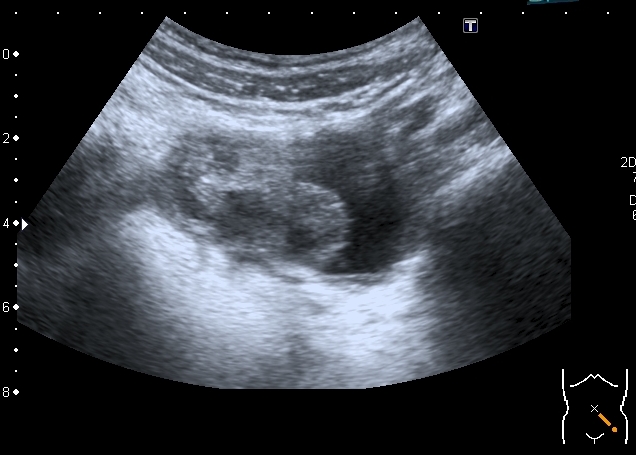

Девочка 14 лет, в течение последних нескольких дней циркулирует между хирургическим и нефрологическим отделением в связи с болями в животе, изменениями в анализах мочи,дизурическими явлениями.

На УЗИ:

Увеличенная матка с анэхогенным содержимым в полости